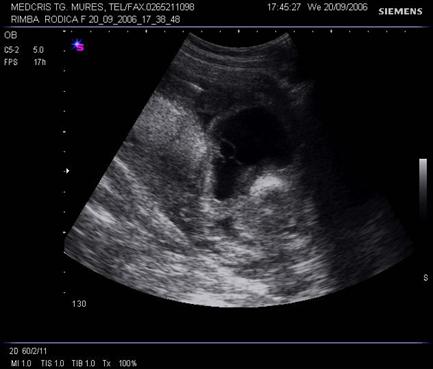

Fig nr. 245. Higroma cystic, la aceeasi sarcina, sectiune transversala

Fig. nr. 247 . Aceeasi sarcina ca in figurile precedente, se remarca atit ascita cat si edemul masiv subcutanat